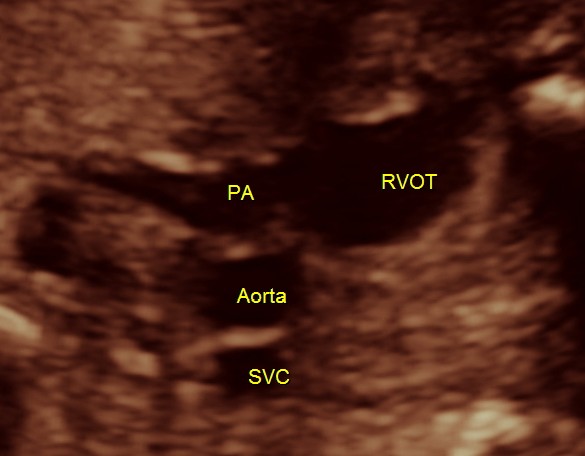

3 vessel view shows a prominent single vessel , which is very suggestive of outflow tract anomalies like transposition of great arteries, double outlet right ventricle , truncus arteriosus and corrected transposition of great arteries.

Under normal circumstances the chamber in front of descending aorta is left atrium ; and the aorta arises from the left ventricle which has no trabeculations ; the pumonary artery which divides into the two branches arises from the anterior right ventricle and crosses over the aorta .

here we can see the pulmonary artery with its two branches arising from the lower (left) ventricle .and the aorta arising from the anterior (right ) ventricle.

pulmonary artery dividing into two